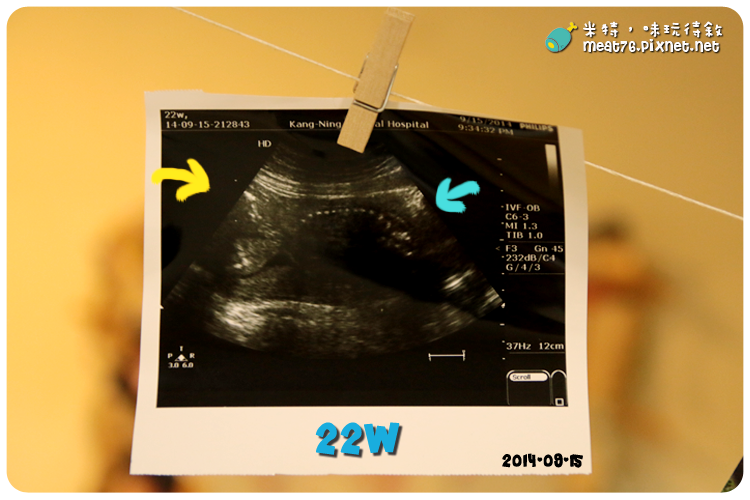

黃色箭頭是寶寶的頭,藍色箭頭是寶寶的屁股,中間白色點點連成的線就是寶寶的脊椎嘍!

至於超音波照片右邊的英文跟數字醫生一直都沒有特別解釋,

是之前看了Babyhome的文章才知道那些密碼代表著什麼,

不過發現...我寶寶的超音波上的密碼完全沒有一樣的,下次產檢一定要問問醫生到底代表什麼意思~